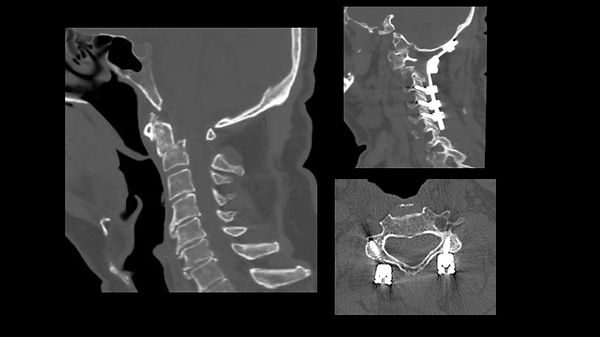

Possono coinvolgere la giunzione cranio-cervicale e le prime due vertebre cervicali (C0-C1-C2) oppure il rachide sub-assiale (C3-C7). Le fratture stabili vengono trattate con collare cervicale tipo Philadelphia a permanenza. Le fratture instabili richiedono un trattamento chirurgico. Per le fratture alte, in base al tipo di frattura, viene effettuata una artrodesi occipito-cervicale, una artrodesi C1-C2 oppure lo screwing del dente di C2 con accesso anteriore. Le fratture del rachide sub-assiale vengono trattate con artrodesi per via anteriore (con cage e placca) o per via posteriore con viti nelle masse laterali. In alcuni casi, per fratture complesse o inveterate, è necessaria una stabilizzazione a 360° con approccio combinato anteriore e posteriore.

Frattura di C2 inveterata